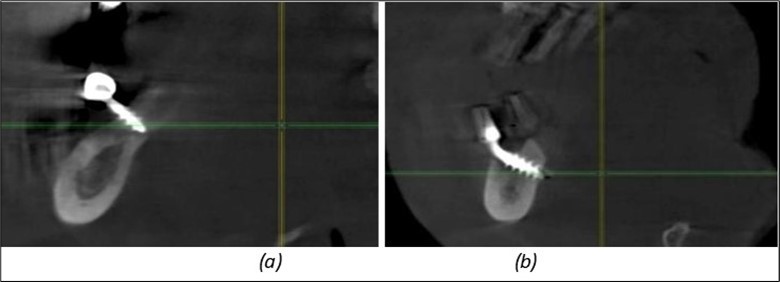

Figure 12.Implants fixed distally in quadrant 4 with fixation at the level of the mylohyoid line: (a) The most distal implant fixed in unaffected bone from the previous restoration; (b) The implant fixed in the area where the two stage implant was removed.